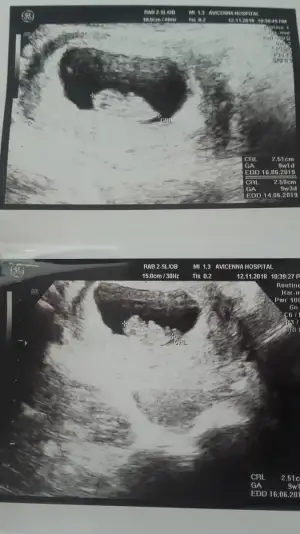

Ayyy o zaman herseyini gorursun Allahin izniyle canimhttps://www.gebelikhesaplama.com/beta-hcg-hesaplama/ buna göre gene 1 kasımda 6 haftalık oluyor suan 7 hafta filan olmam lazım 2 gun sonra zaten randuwum bakalım ne cıkcak eylülayında yumurtlama haftamda tutmus olabilir galiba